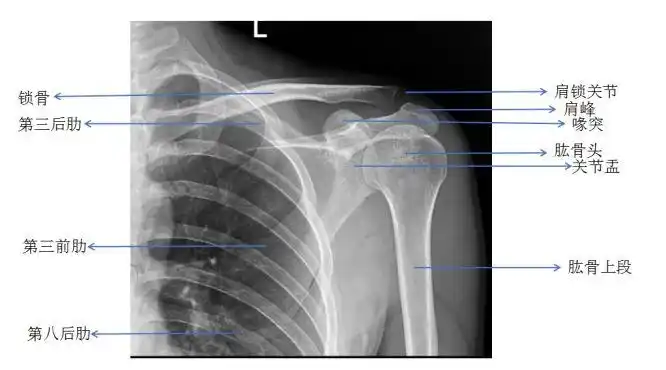

肩关节的摄影体位